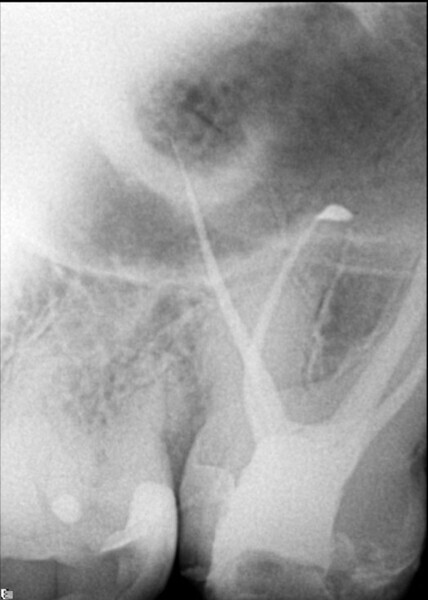

I asked for an i-CAT scan to be taken in order to better understand what was going on. Studying the horizontal view of the 3D image, the level of calcification in the pulp chamber compared with the pulp chamber of the first molar could be seen clearly (Fig. 2).

Fig. 2: Horizontal cross section taken from the i-CAT scan (DEXIS) showing total calcification of the root canal orifice at the level of the cemento-enamel junction, in comparison with the first molar.